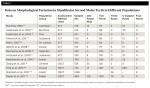

Table 1 is a tabulation of various studies representing data on morphological variation in mandibular second molar teeth in different populations.11-17,19,26-30 Table 2 lists various case reports of mandibular second molars with four roots.7,8,10,31-33

The number of roots in a mandibular second molar typically ranges from one to three.5 Incidence of the presence of a third root was 2.8% in a population of Mongolian origin, 1.8% for a Black population, and 1.7% in Caucasians.24 In the mandibular second molar the most prevalent canal pattern in the mesial root is type III, followed by type IV and type II; the most prevalent canal pattern in the distal root is type I, with type II and type IV (Mongoloid trait) occurring rarely.11,14 The prevalence of three-rooted mandibular second molars in an Indian population was 8.98% and 1.2% in a Thai population, while it was 0% in a Burmese population.12 A high prevalence of c-shaped canals and a low prevalence of three roots were observed in the mandibular second molars of a Korean population.25 In some population groups, such as Indian and Jordanian, two roots and three canals are more common, followed by c-shaped canals.12,17Even incidence of four roots in first molars is 0.04% in a Japanese population, with several case reports documenting this.6

Cases of the following anatomical configurations have been reported: mandibular second molar with three separate independent mesial roots and one distal root; mandibular second molar with two mesial and two distal independent roots; and mandibular second molar with two mesial and one distal root with radix entomolaris.7-10 Although numerous studies have been undertaken, statistical data for various populations regarding incidence of four-rooted mandibular molars still has not been presented, except for 0.55% in the Israeli population.11-19